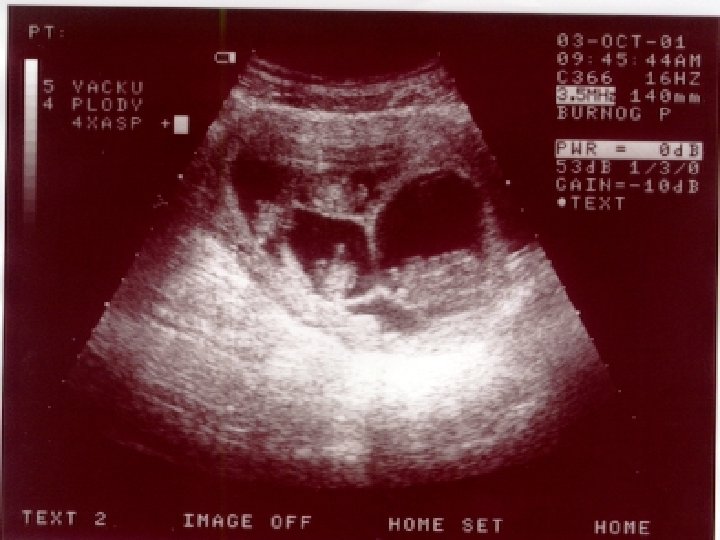

Ultrazvukový screening • UZ screening I. trimestru v 10 -13. t. g. (počet plodů, velikost, projasnění na krčku plodu, přítomnost nosní kůstky – riziko Downova syndromu) • UZ screening II. trimestru ve 20 t. g. (detekce poznatelných vrozených vývojových vad a nepřímých známek vrozených chromosomových aberací u plodu)

UZ -prenatální kardiologie ve 21. t. g. (detekce poznatelných srdečních vad) • Vrozené srdeční vady jsou nejčastější vývojovou vadou u člověka, často spojené s dalším postižením • Prenatální diagnostika srdečních vad vyžaduje specializovanou erudici a zkušenost • Poznání srdeční vady u plodu umožňuje dle závažnosti modifikovat další postup (ukončení těhotenství, léčba plodu, sledování a porod na specializovaném pracovišti)